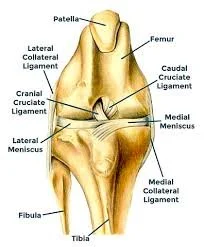

ACL Tear in Dogs: Symptoms, Diagnosis, Surgery, and Recovery

ACL tears are one of the most common orthopedic injuries in dogs and often cause sudden hind leg limping. Learn the symptoms and treatment options for cruciate ligament injuries.

Understanding Ruptured Cranial Cruciate Ligament (CCL) in Dogs

A ruptured cranial cruciate ligament (CCL) is one of the most common and painful knee injuries in dogs. This in‑depth guide explains what causes CCL tears, how to recognize the signs, the pros and cons of each surgical option, what recovery looks like, and how to support long‑term joint health. Whether your dog has a sudden limp or chronic stiffness, this article helps you understand the condition and make informed decisions about treatment.